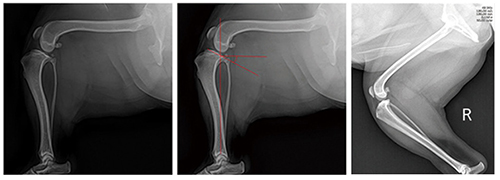

■ TPA를 측정하는 방법 - X-ray 촬영

• The medio-lateral view

- 무릎을 굽혀 tarso-crural joint가 90˚가 되게 촬영한다.

- Tibia는 돌아가지 않게 cassette에 평행하게 촬영한다.

- Femoral & tibial condyles이 완전히 겹쳐질 수 있게 촬영한다(angular or torsional deformity가 없다는 가정하).

- The beam center는 무릎에 오게.

■ TPA를 측정하는 방법 - TPA 측정

• Medial tibial condyles의 cranial & caudal extents를 이어주는 선을 그린다(Tibial plateau slope).

• Tibia의 inter-condylar tubercles과 rotation of the talus의 중심부를 연결하는 선을 그린다(Tibial long axis).

• Tibial plateau slope와 tibial long axis line이 만나는 곳에서 tibial long axis의 직각으로 선을 그어 그 선과 TPS가 이루는 각도를 측정한다(TPA).